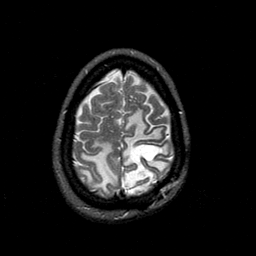

MR Study #1 -- Slice #43